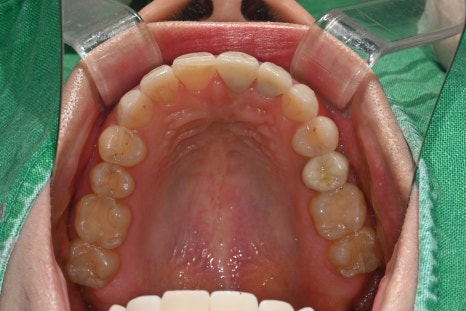

1.기존 크라운 제거 후 치아 상태 재확인

변색과 경계 문제를 해소하기 위해 기존 보철물 제거 후 잇몸 라인과 치아 모양을 새롭게 설계했습니다.

2.오브제로 퓨어 라미네이트 4개 지대치 형성 및 스캔

가능한 범위 내에서 삭제량을 줄였고, 구강스캐너로 정확한 형태를 채득했습니다.

3.전치부 크라운 2개 디자인 및 인상 채득

앞니 중심축과 교합 높이를 정확하게 형성했습니다.

4.임시치아 장착 후 기능·발음·심미 체크

환자분의 말하기 습관, 미소선, 발음 시 바람 빠짐

등을 꼼꼼히 확인했습니다.

5.최종 보철물 장착 및 오브제로 세팅

치료 당일, 전체 교합·색상·광택을 조정한 후 영구 접착

을 완료했습니다.

6.1주 후 Follow-up 점검

교합 안정도, 잇몸 적응 여부 등을 체크했고,

모든 영역에서 양호한 결과를 확인했습니다.